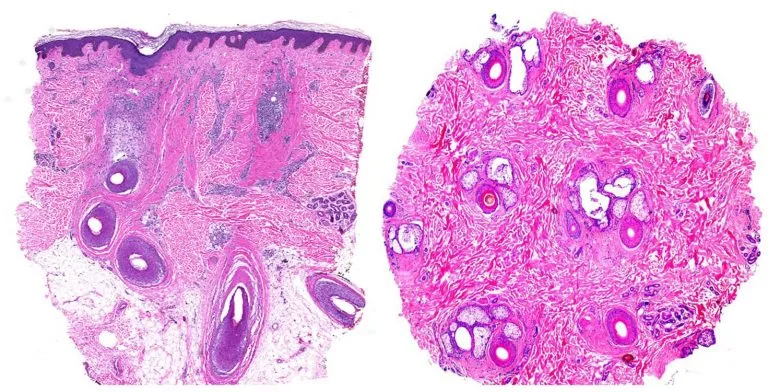

En casos de duda diagnóstica puede resultar clave la realización de una biopsia (o dos) para estudio anatomopatológico. Habitualmente se realiza mediante la toma de un cilindro punch de 4 mm guiada por tricoscopia, para seleccionar una zona representativa de alta actividad y así optimizar el estudio. Para un estudio óptimo, se recomienda la toma de dos biopsias, para realizar cortes longitudinales y transversales de la muestra. Sin embargo, con una buena orientación clínica, en la mayoría de casos será suficiente con una muestra. En caso de las alopecias cicatriciales los cortes más útiles son los longitudinales, mientras que los transversales son clave para las alopecias no cicatriciales.